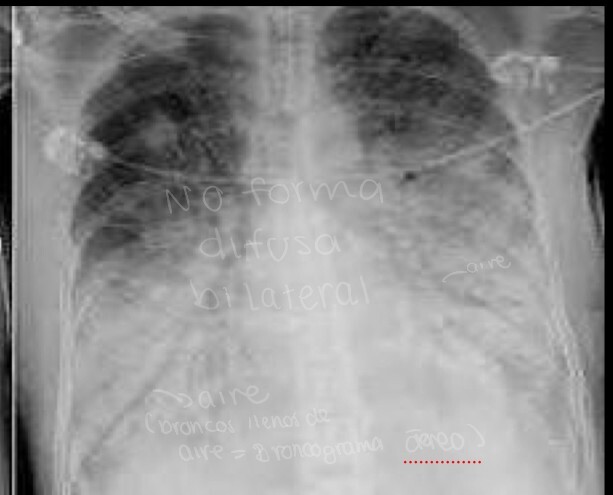

en este patrón no podemos ver estructuras, se verá blanco muy sólido, veremos una radiopacidad en RX o una hiperdensidad en TC de forma irregular y difusa

A

en el patrón de consolidación/ ocupación alveolar también podremos ver los bronquios llenos de aire, como se le llama a esto

broncograma aéreo

que patrón pulmonar es

consolidación